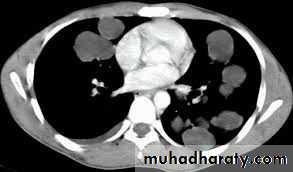

1. CXR 2. CT scan

4) Bilateral and multiple cysts

thoracic surgery